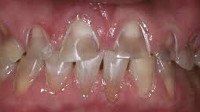

В начальной стадии происходит потеря блеска эмали в области ограниченного участка вестибулярной поверхности зуба. На данном этапе заметить признаки начавшегося эрозивного процесса можно только после высушивания поверхности зуба струей воздуха или нанесения на участок поражения 5% йодной настойки - в этом случае происходит желто-коричневое окрашивание участка эрозии.

Первоначально эрозивный дефект представляет собой округлый или овальный очаг чашеобразной формы с твердым, гладким и блестящим дном. По мере расширения и углубления очага может происходить полная утрата эмалевого слоя и обнажение дентина. При I и II степени эрозии зубов дефект имеет белесоватый цвет; при III степени патологического процесса появляется светло-желтая или коричневая пигментация.